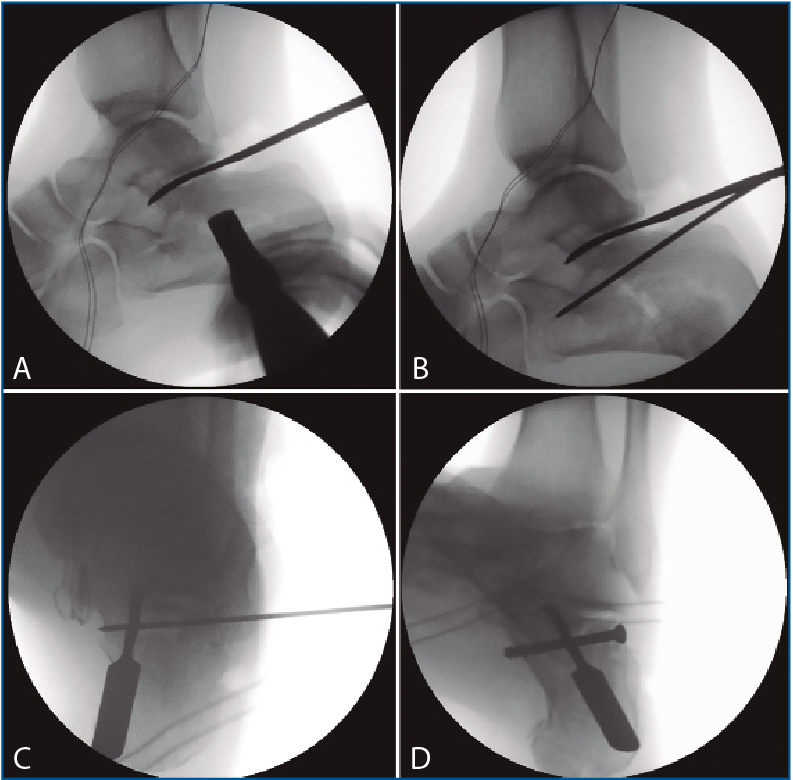

En los 4 casos con osteosíntesis percutánea, una vez levantado el fragmento, se realiza una fijación provisional con agujas de 1,8 mm (Figuras 4B y 4C), que podemos emplear, además, para manipular el fragmento y mejorar la corrección. A continuación, se procede a la inserción de los tornillos canulados de 3,5 mm de lateral a medial, solidarizando el fragmento lateral con el anteromedial (Figura 4D). Se debe combinar la visión artroscópica con una visión radiológica que nos confirme la posición y longitud adecuada de los tornillos.

Figura 4. A: control de escopia intraoperatoria (perfil) de la lesión reducida con ayuda de periostotomos; B: control de escopia intraoperatoria (perfil) tras insertar la primera aguja mientras se mantiene la reducción con un periostotomo; C: control de escopia intraoperatoria (axial de calcáneo) tras insertar la primera aguja mientras se mantiene la reducción con un periostotomo; D: control de escopia intraoperatoria (axial de calcáneo) tras colocación del primer tornillo de osteosíntesis.